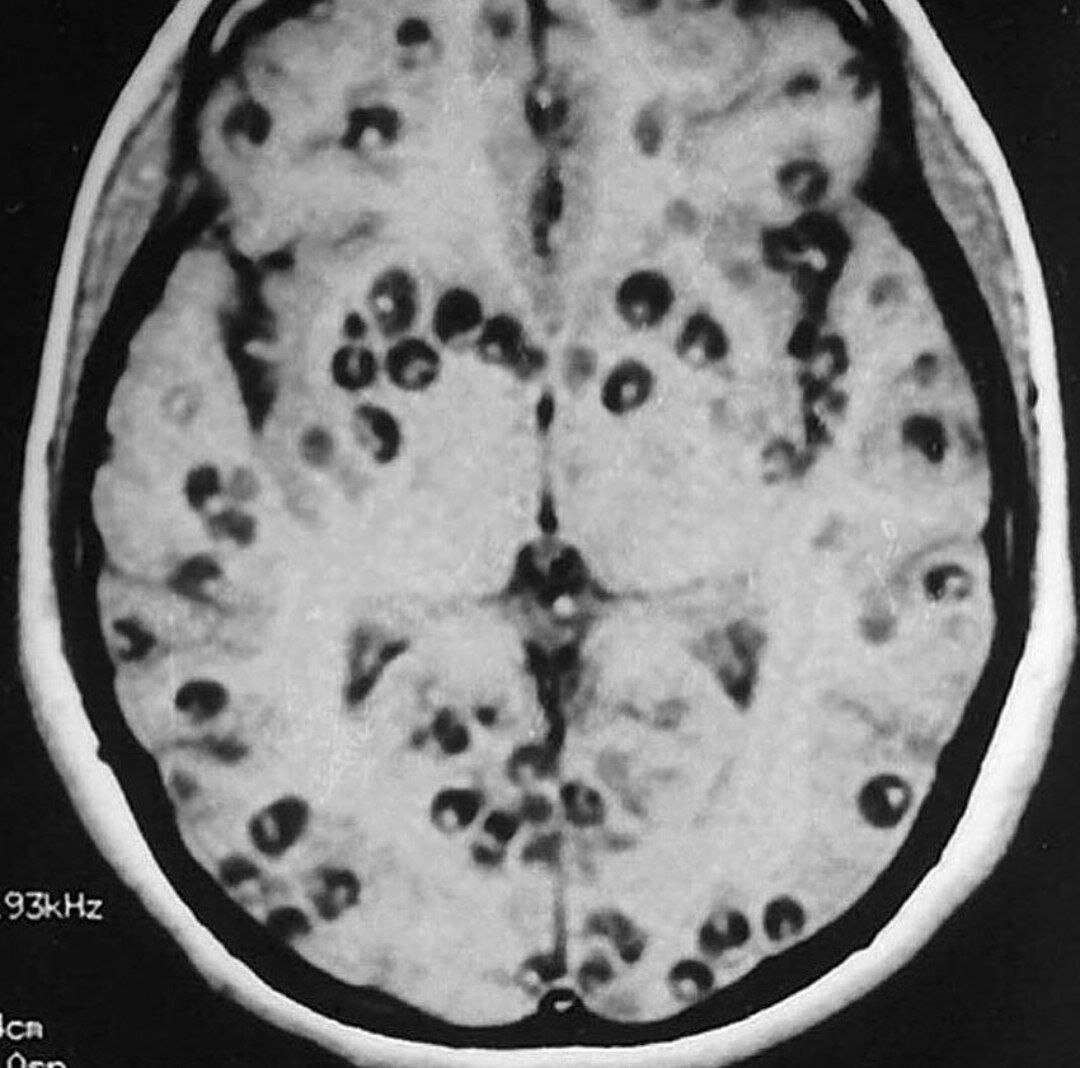

Нейроцистицеркоз

Нейроцистицеркоз – это паразитарное заболевание нервной системы, вызываемое личинками свиного цепня. Человек заражается при попадании яиц свиного цепня в желудочно-кишечный тракт. Первые симптомы чаще всего появляются через 5-7 лет после инфицирования. Чаще проявляется судорогами, повышением внутричерепного давления, нарушением интеллектуальных функций, но может протекать бессимптомно. Характерно волнообразное течение с периодами обострения и относительного улучшения состояния. Диагностика довольно трудна. Для лечения применяют как медикаментозные методы, так и оперативные вмешательства.